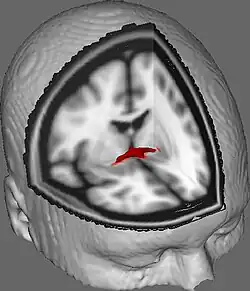

Dans une section sagittale, la commissure antérieure est de forme ovale, ayant un long axe vertical qui mesure environ 5mm.

En 1992, Laura Allen et Roger Gorski de l'UCLA ont mesuré les commissures antérieures de 30 hommes homosexuels, 30 hommes hétérosexuels et 30 femmes hétérosexuelles. Ils ont constaté que les précommissures des trois groupes étaient significativement différentes les unes des autres, les hommes homosexuels ayant la plus grande commissure antérieure, suivis des femmes hétérosexuelles, puis des hommes hétérosexuels, qui avaient les plus petites commissures antérieures[7].

De plus, une étude de Lasco et al. (2002) a présenté : «Nous avons examiné la surface transversale de la CA dans le matériel post-mortem de 120 personnes et n'avons trouvé aucune variation dans la taille de la CA avec l'âge, le statut VIH, le sexe ou l'orientation sexuelle»[10].